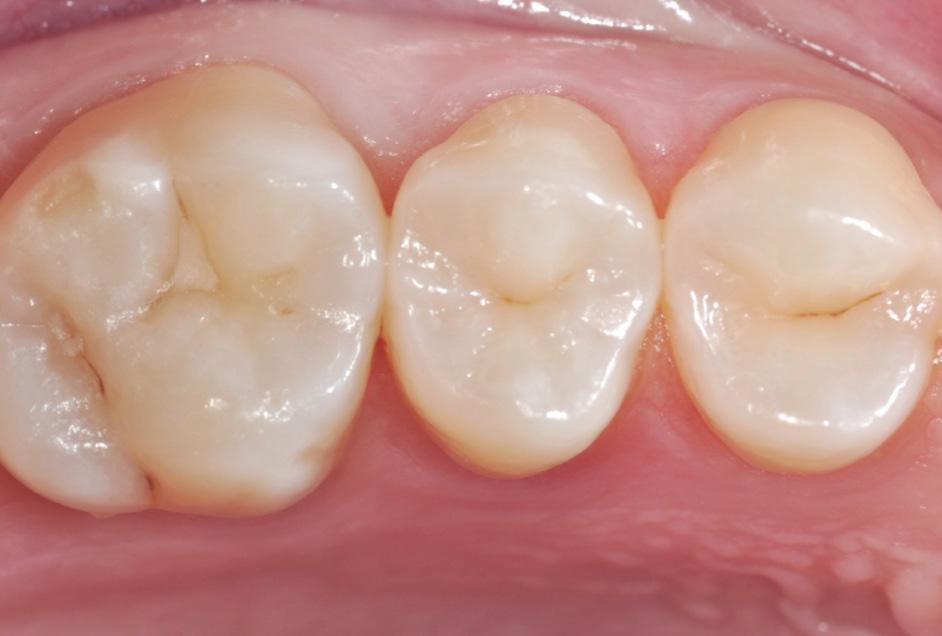

Fig. 9: After removal of the matrix band, the composite was cured for 10 seconds on both the buccal and lingual surface.* Fig. 10: After finishing and pre-polishing, the 3M™ Sof-Lex™ Diamond Polishing System on moist surface was used to create a high gloss polish.

Fig. 11: Final outcome using 3M™ Filtek™ One Bulk Fill Restorative.